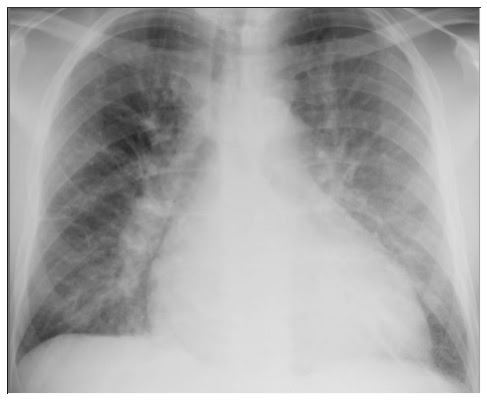

Délia, 68 anos, negra, casada, natural de Tocantins(MG), procedente de Vila Velha está internada no hospital para tratamento de osteomielite de quadril após colocação de prótese articular. Paciente relata alergia a ibuprofeno. Diabética e hipertensa, com diagnóstico de insuficiência renal crônica com tratamento conservador. Inicialmente a paciente fez uso de oxacilina, porém quando a cultura ficou pronta mostrou crescimento de S. aureus resistente a oxacilina. O médico assistente iniciou outro tratamento para a paciente de acordo com o antibiograma. Após cerca de 14 dias do uso do novo antibiótico a paciente começou a apresentar tosse e falta de ar. Foi feito radiografia de tórax que mostrou ( figura abaixo). Solicitado broncoscopia que evidenciou lavado broncoalveolar com presença de eosinófilos. Responda as três questões abaixo:

1) Daptomicina - lipopeptideo

2) Pneumonia eosinofílica;

3) Pois é o antibiótico de escolha para Staphylococcus aureus resistente à meticilina/oxacilina (MRSA)